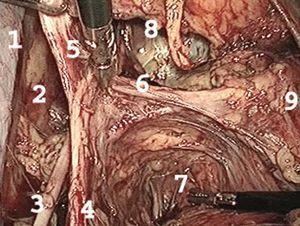

La intervención se inició con la sección distal de los ligamentos redondos y el desarrollo de las fosas paravesicales hasta la fascia endopélvica y una linfadenectomía pélvica bilateral hasta la bifurcación de la arteria ilíaca primitiva. Los ganglios se depositaron en una endobolsa que se extrajo por vía vaginal al finalizar la intervención. Seguidamente, se realizó la exposición de la fosa pararrectal hasta el músculo elevador del ano (fig. 2). En los últimos 14 casos se ha realizado la disección de los nervios esplánicos, situados en la cara posteroinferior del parametrio, para preservar la inervación parasimpática del recto y la vejiga (fig. 3). A continuación se realizó la sección de la arteria uterina en su origen y la resección radical del parametrio con una pinza bipolar (Ligasure) o bisturí armónico (ultracisión) hasta los nervios esplánicos, previamente expuestos (fig. 4). En los primeros casos la resección del parametrio se realizó en bloque utilizando endocortadoras mecánicas y, más tarde, el Ligasure de 10 mm (Atlas, Tyco). A medida que se adquirió experiencia, se profundizó en la disección de las estructuras anatómicas del parametrio, lo que posibilitó la sección individualizada de estas estructuras que comprenden, en sentido descendente, arteria uterina, venas uterinas, venas de drenaje vesicouterinas y arteria rectal media. La hemostasia y la sección se realizaron con instrumental de 5 mm (Ligasure o ultracisión).

Figura 2.Detalle de la fosa pararrectal: vena ilíaca externa (1); pared pélvica (2); nervio obturador (3); tronco anterior de la arteria ilíaca interna (4); arteria vesical superior (5); arteria uterina (sección en su origen) (6); fosa parrectal (en el fondo se visualizan las raíces nerviosas esplánicas) (7); fosa paravesical (8), y útero (9).